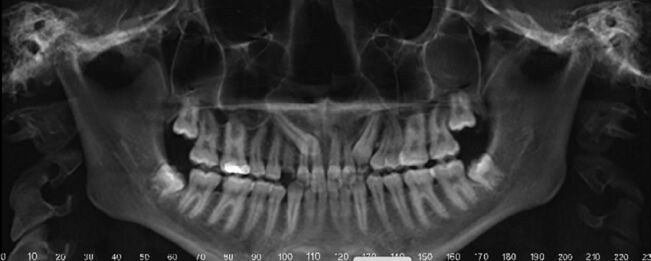

35.5歲男童因右下牙痛求診,拍攝之放射線影像如圖所示;先注射2% lidocaine with 1:100,000 epinephrine後開始後續處置,下列何者錯誤? (A)第一乳臼齒不宜施行活髓治療(vital pulp therapy) (B)第一乳臼齒可考慮拔除 (C)第一乳臼齒牙根吸收非生理性現象 (D)該麻醉藥物的最大劑量是6.0 mg/kg

40.3歲男童因牙齒缺損及變色前來求診,拍攝放射線影像如圖示,下列敘述何者正確? (A)左側上顎正中乳門齒發生牙根內吸收 (B)左側上顎正中乳門齒牙冠應呈粉紅色 (C)此案例牙根吸收的原因可能是外傷 (D)此案例的診斷為根管堵塞(obliteration)